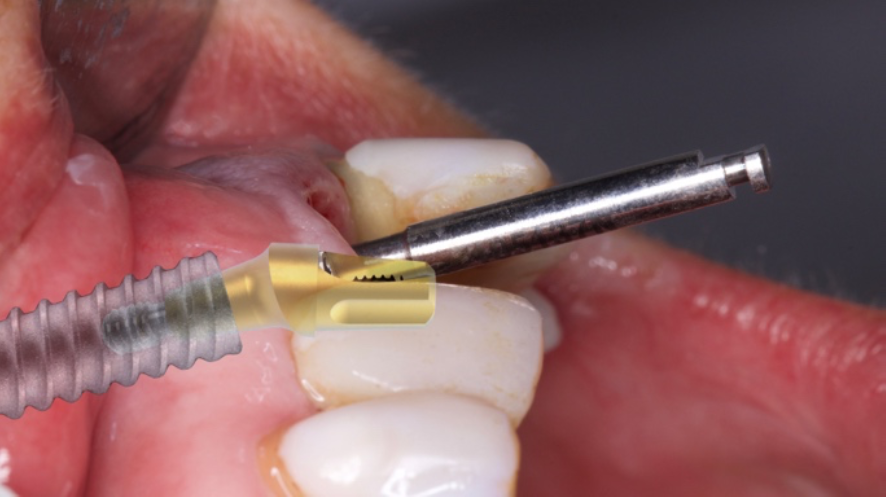

O objetivo deste relato de caso é mostrar a utilização do implante de diâmetro reduzido em região anterior de maxila com limitação óssea, respeitando a anatomia do processo alveolar e consequentemente utilizando um componente angulado para corrigir a posição da saída do parafuso para confecção de uma prótese aparafusada.

Conforme discutido na literatura, a colocação imediata de implantes na zona estética requer que o clínico tenha conhecimento e experiência em diversas áreas. Isso inclui diagnóstico estético, técnicas de extração minimamente invasivas, procedimentos cirúrgicos plásticos orais (por exemplo, enxerto de tecidos duros e moles) e colocação de implantes tridimensionais (3D) precisos com o uso de um implante mais estreito (3,3 mm a 4,3 mm), o que garante um espaço vestibular de pelo menos 2 a 3 mm adjacente à parede do alvéolo bucal intacto. Isso pode ser pré-planejado com uma análise cuidadosa através de exames de imagem para uma melhor compreensão do plano restaurador. O uso de técnicas avançadas de imagem, como a tomografia computadorizada de feixe cônico (CBCT), pode auxiliar no planejamento preciso do tratamento e na colocação do implante.